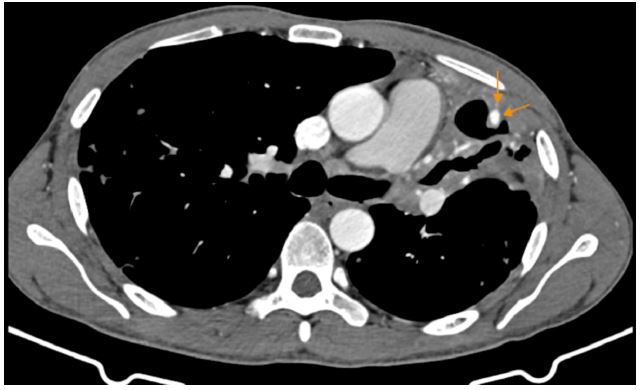

Subsequently, the patient was referred for CT-guided percutaneous intervention. Under CT guidance, an 18G needle was advanced into the pseudoaneurysm, and contrast injection verified intraluminal positioning. Embolization was performed with NBCA: lipiodol at a 1:2 ratio. Post-procedural contrast-enhanced CT demonstrated complete filling of the pseudoaneurysm sac with glue, indicating successful occlusion. The patient experienced no further hemoptysis and was discharged after 4 days, with initiation of standard anti-tuberculosis therapy.

Figure 4: (A) CT-guided intervention with an 18G needle puncturing the pseudoaneurysm, followed by injection of NBCA glue mixed with lipiodol at a 1:2 ratio. (B) Post-procedural assessment shows complete occlusion of the pseudoaneurysm. A small amount of glue is seen refluxing into a minor branch of the pulmonary artery. Clinically, the patient had no further episodes of hemoptysis.

Was the pseudoaneurysm observed in the above clinical case truly a Pulmonary Artery Pseudoaneurysm (PAP)? The absence of a pseudoaneurysm on DSA of the left pulmonary artery does not entirely exclude its presence, especially given its peripheral location and small size. The affected branches exhibited wall damage, anatomical complexity, and altered flow dynamics, which hindered successful selective catheterization. Upon successful direct puncture of the pseudoaneurysm, NBCA glue was observed to pool in a focal area and reflux into a small pulmonary arterial branch, indicating retrograde flow and confirming communication with the pulmonary circulation.

In situations where endovascular access fails or is anatomically unfeasible, percutaneous puncture techniques may be considered, although they carry inherent risks such as pneumothorax or pseudoaneurysm rupture if not performed with precision [3,6]. In the reported case, the initial attempt at direct puncture under DSA guidance failed and resulted in a temporary recurrence of hemoptysis. Subsequently, CT-guided intervention allowed for precise localization of the pseudoaneurysm and accurate delivery of glue, achieving definitive therapeutic success. Using a higher NBCA-to-lipiodol ratio (1:2) increased the mixture’s viscosity, limiting glue dispersion and reducing the risk of non-target embolization.

The successful outcome in this case further supports the potential role of direct percutaneous pseudoaneurysm puncture as a salvage technique when standard endovascular approaches fail. However, it should be regarded as a last-resort option, reserved for institutions equipped with appropriate imaging modalities, technical expertise, and the capacity to manage complications. Proper selection of glue concentration and volume, accurate needle placement, and close post-procedural monitoring are critical to maximize treatment efficacy and minimize risks.